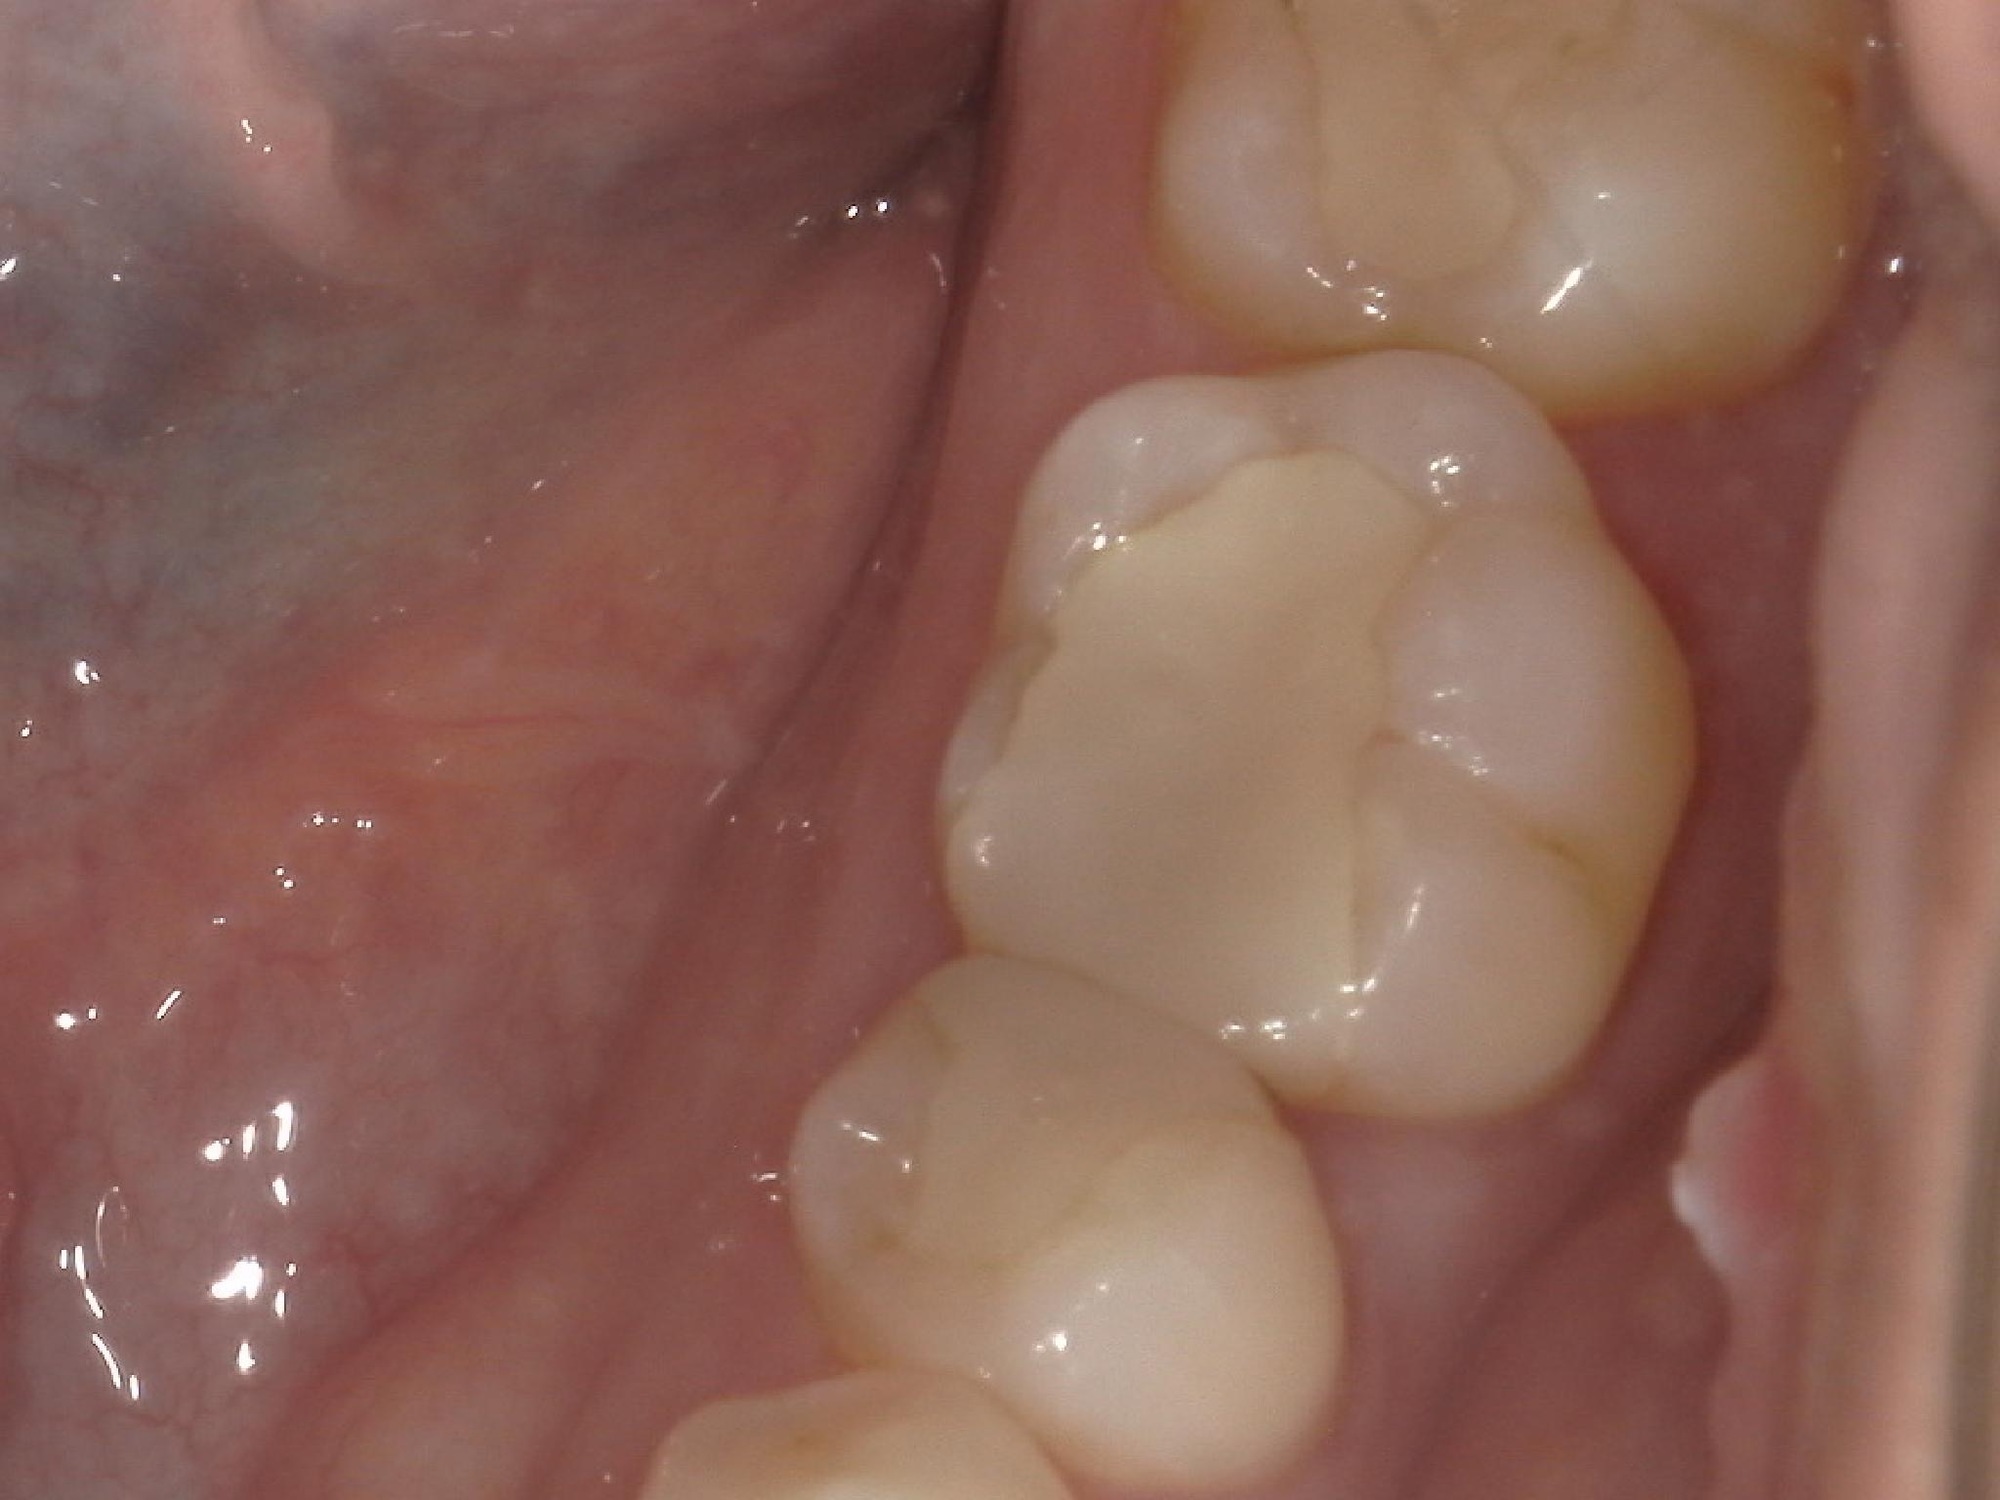

左下の前から6番の歯の虫歯治療の症例を紹介させていただきます。

こちらは保険診療で、コンポジットレジン修復で治療をしております。